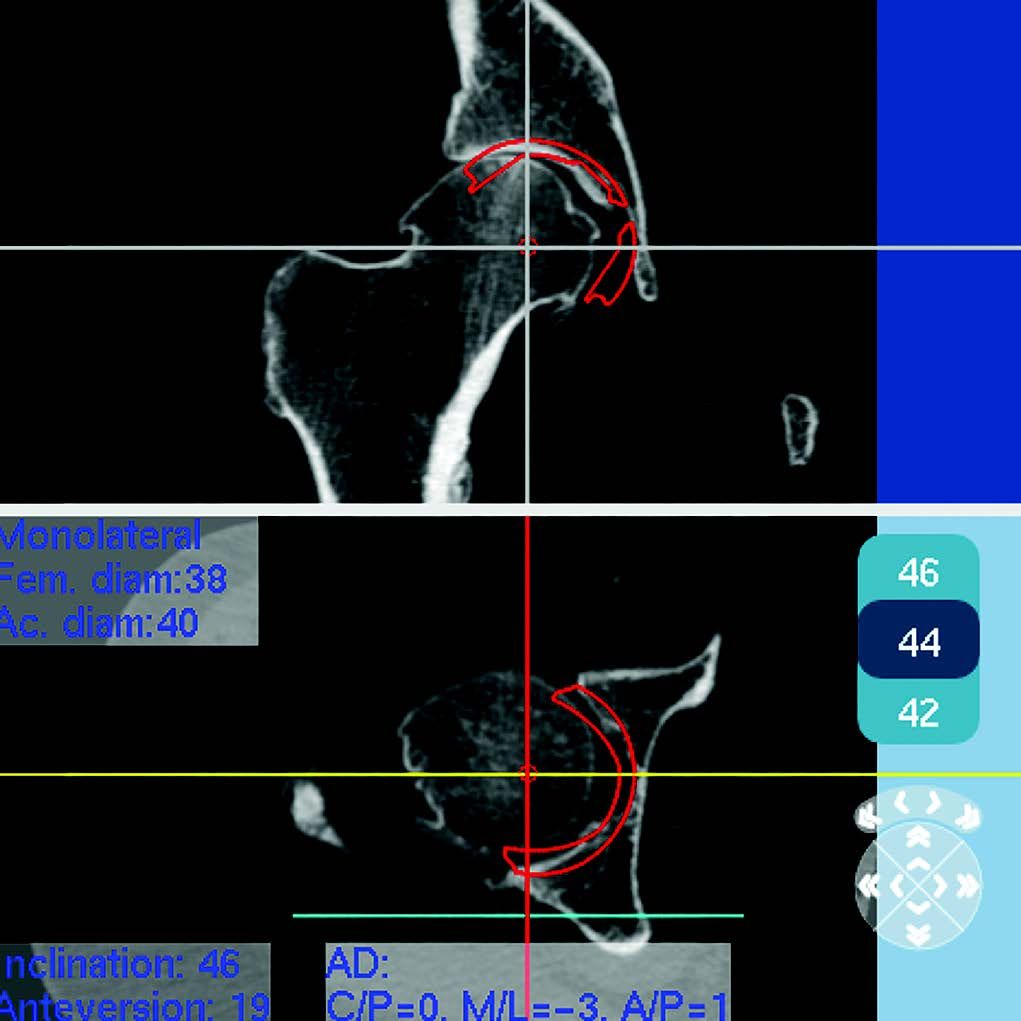

Step 4: acetabular planning: 3D acquisition is used to measure the native acetabulum and to select the position of the acetabulum (Fig. 4).

Currently there is no difference in accuracy between using layer planning or software planning from standard x-rays. Caution should even be exercised when using automated calibration (18).

In my experience (prospective study on 100 consecutive records) the accuracy of acetabulum size CT planning is remarkable, with an agreement rate between the planned acetabulum and the implanted acetabulum of 94 % and 100 % to the nearest size. This type of planning meant I was able to place smaller implants and to use cementless acetabular components only. Acetabular implants in women are almost exclusively size 46 and 48. Dispersion is higher in men, with an average acetabular component size of 52. The CT-scan also makes it possible to evaluate the condition of the anterior wall and to determine whether the acetabulum is likely to overrun in contact with the psoas. Seeing the bone acetabulum on the CT-scan makes placement in situ and adjustment of inclination and anteversion easier. With this system I don't believe an image intensifier or navigation is necessary.